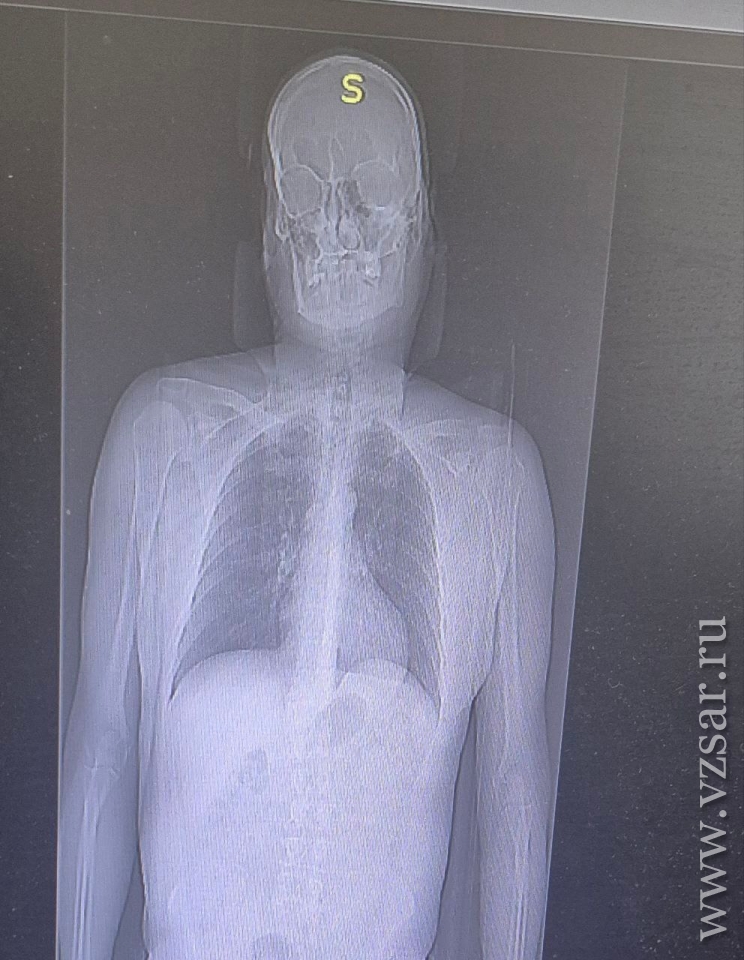

Пациент отделался переломами двух ребер и ушибами мягких тканей. Благодаря оперативной диагностике (КТ, УЗИ), адекватному обезболиванию и грамотно оказанной медицинской помощи, сейчас пациент стабилен и готовится к выписке уже на следующей неделе.